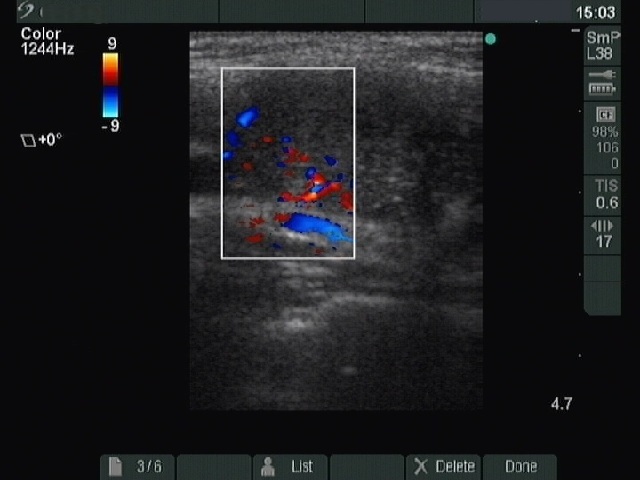

Ultrasonography : there was a moderately hypoechogenic inhomogeneous nodule with microcalcifications in the right lobe. The borders of the nodule were blurred. The intranodular blood flow was increased.